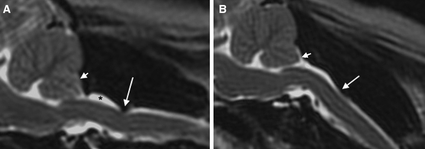

April 2020:

In an

April 2020 article, a team of Ohio State veterinary researchers

(Sarah M Weber, Eric T Hostnik [right], Wm Tod Drost, Alessandra N Hamlin, Marc

A Ledesma, Lauren Timperman, Ashley C. Hechler, Lynette K Cole) compared

high-field magnetic resonance imaging (MRI) with multidetector computed

tomography (CT) for grading Chiari‐like malformation (CM) and

syringomyelia (SM) in 30 cavalier King Charles spaniels. (See Figure

2, below.) The dogs had

been MRI and CT scanned previously for Dr. Lynette Cole's study of

primary secretory otitis media (PSOM) in the breed. The current study

also included three classes of observers with different levels of

experience -- two American college of veterinary radiology diplomates

(DACVR) and two second-year veterinary radiology residents and two small

animal veterinary interns. They point out the reason for the study is

that, "Computed tomography is financially cheaper, shorter in

acquisition time, more accessible to general practitioners, and requires

less anesthetic drugs/time." The results of the study support the

hypothesis that the overall agreement and the agreement between observer

groups of similar experience levels is higher using MRI compared to CT.

As expected, the accuracy for diagnosis by experienced radiologists of

cerebellar herniation and SM using MRI was higher than CT. However, CT

had a higher accuracy among the second-year radiology residents and

veterinary interns for identifying cerebellar herniation, which

countered the investigators' hypothesis that MRI is a better tool for CM

evaluation. They concluded:

"Computed tomography does not replace MRI for the diagnosis and classification of CM and SM in CKCS. The accuracy and agreement for identifying cerebellar herniation and SM in experienced observers was higher utilizing high-field MRI compared to multislice CT. Breeding programs for CKCS should continue to utilize MRI for antemortem diagnosis of CM and SM to help improve the genetic pool and minimize the risks for neuropathic pain brought about by CM and SM. Individuals with greater diagnostic imaging experience (DACVR) resulted in better agreement for both MRI and CT and higher sensitivity, specificity, and accuracy for cerebellar herniation and SM. Magnetic resonance imaging interpreted by experienced observers should remain the standard tool for CM and SM screening programs."